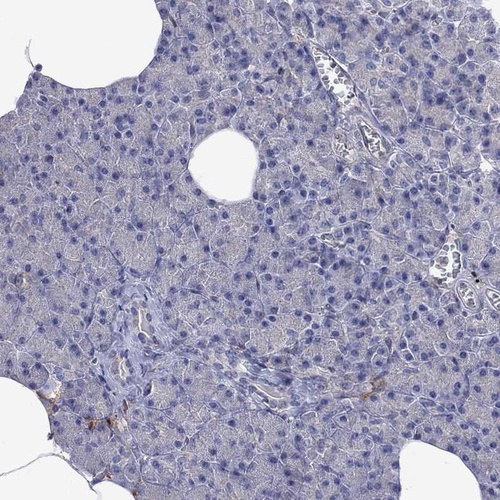

Immunohistochemistry analysis in human epididymis and pancreas tissues using Anti-MTHFR antibody. Corresponding MTHFR RNA-seq data are presented for the same tissues.